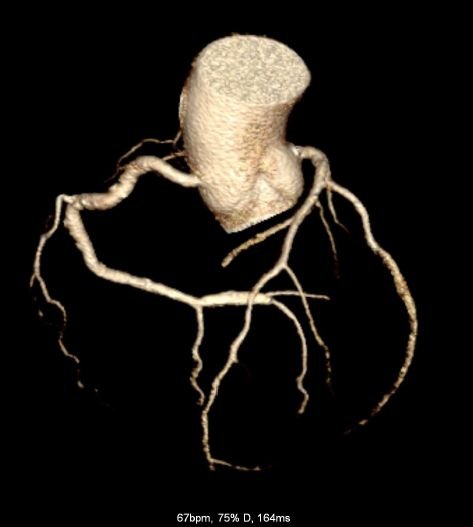

CT Heart

CT Cardiac Anatomy